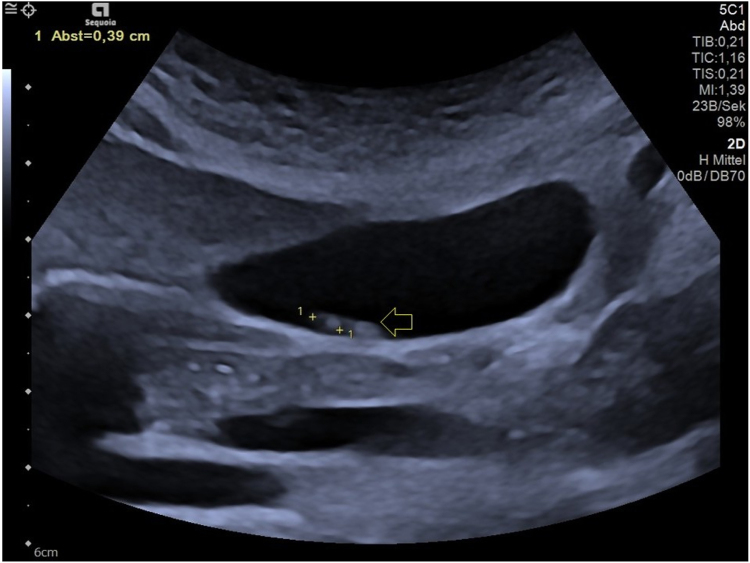

Case report: A 41-years-old male patient with sonographically confirmed, culture-negative endocarditis accompanied by repeated fever episodes received 4g ceftriaxone per day next to ampicillin and gentamicin as an element of his antibiotic therapy. At day 4 of treatment, signs of gall bladder sludge and biliary pseudolithiasis were first seen in sonography. At day 17, abdominal pain over 30 min and increased liver and pancreatic enzymes pointed towards temporal duct obstruction as a complication and ceftriaxone therapy had to be preterm cancelled. A sonographic work-up of the stepwise improvement of the sonographic findings after the end of the ceftriaxone therapy is provided, a reemergence of endocarditis was not observed.